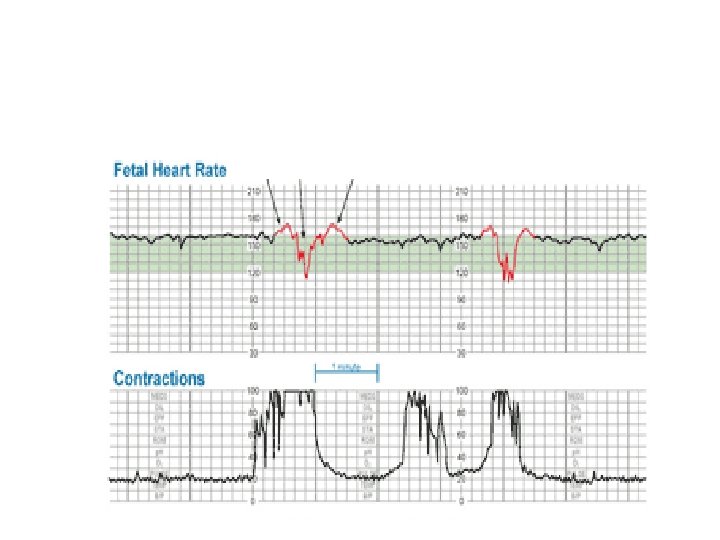

Variable Deceleration Abrupt decrease in FHR of > 15 beats per minute measured from the most recently determined baseline rate. The onset of deceleration to nadir is less than 30 seconds. The deceleration lasts > 15 seconds and less than 2 minutes. A shoulder, if present, is not included as part of the deceleration. Variable decelerations may be observed in up to 50% of NSTs. If nonrecurrent and <30 seconds, they are of no clinical significance.

Variable Deceleration Typical: • shoulders Atypical : • Overshoot • Loss of primary shoulder • Slow return to baseline (late component) • Baseline returns to a lower level(after deceleration) • Biphasic(W shape) • loss of variability during deceleration

Classification severity of variable deceleration • Mild: duration < 30 second or depth up to 80 bpm • Moderate : deceleration < 80 bpm • Severe : deceleration < 70 bpm for more than 60 second

Complicated variable deceleration Indicated fetal hypoxia • Tachycardia • Lack of variability • Slow return to baseline • Large amplitude(to 60 bpm or duration 60 second) • Loss of pre and post shouldering • Smooth overshoot